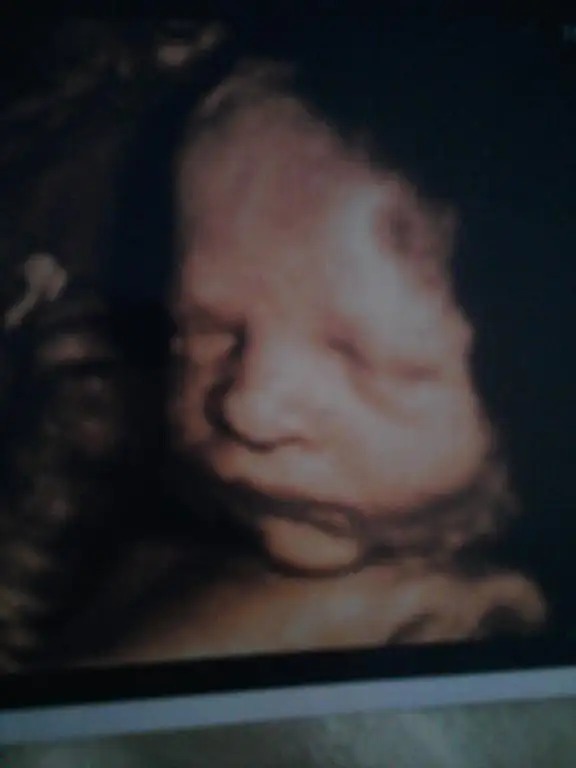

Bakın bu da tipsiz kızım.Aynı babasına benziyorr :)